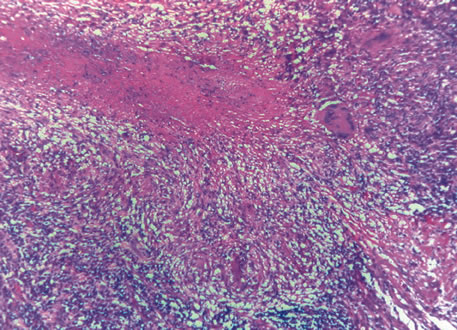

Three histologic patterns of granulomatous inflammation may be seen: diffuse, discrete, and zonal. In diffuse granulomatous inflammation, the epithelioid histiocytes are scattered throughout the involved uveal tissue (Fig. 19). There may be an accompanying background of lymphocytes and plasma cells. Discrete granulomatous inflammation reveals well-circumscribed areas of epithelioid histiocytes (Fig. 20). Zonal granulomatous inflammation consists of a central zone of necrosis and/or polymorphonuclear leukocytes surrounded by epithelioid histiocytes, which is in turn surrounded by a zone of non-granulomatous inflammation consisting of granulation tissue, lymphocytes and plasma cells (Fig. 21).

Fig. 20. Sarcoidosis. Discrete granulomatous inflammation is seen in sarcoidosis. (Hemotoxylin-eosin ×100.)